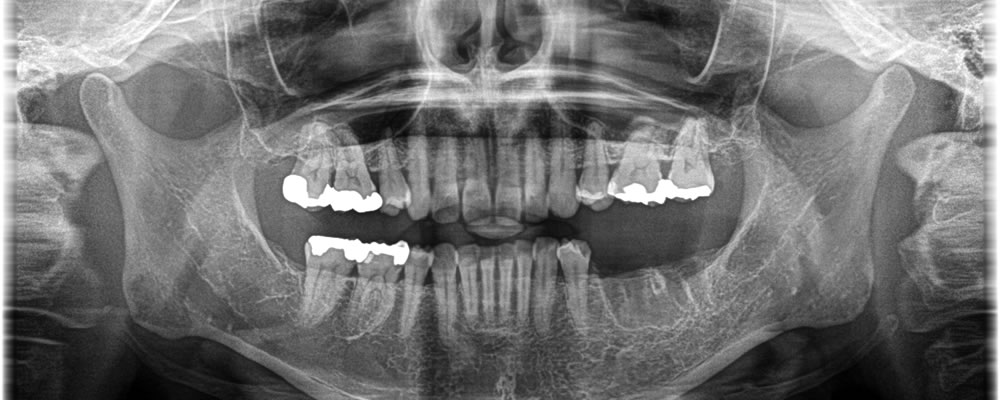

こちらの患者さまは、他院で抜歯された部位に歯を入れたいとのことで来院されました。入れ歯は抵抗があるとのことで治療法を提案したところ、インプラント治療を希望されました。

大臼歯2本分欠損していたため、しっかりと噛み合うよう、インプラントも2本埋入しました。